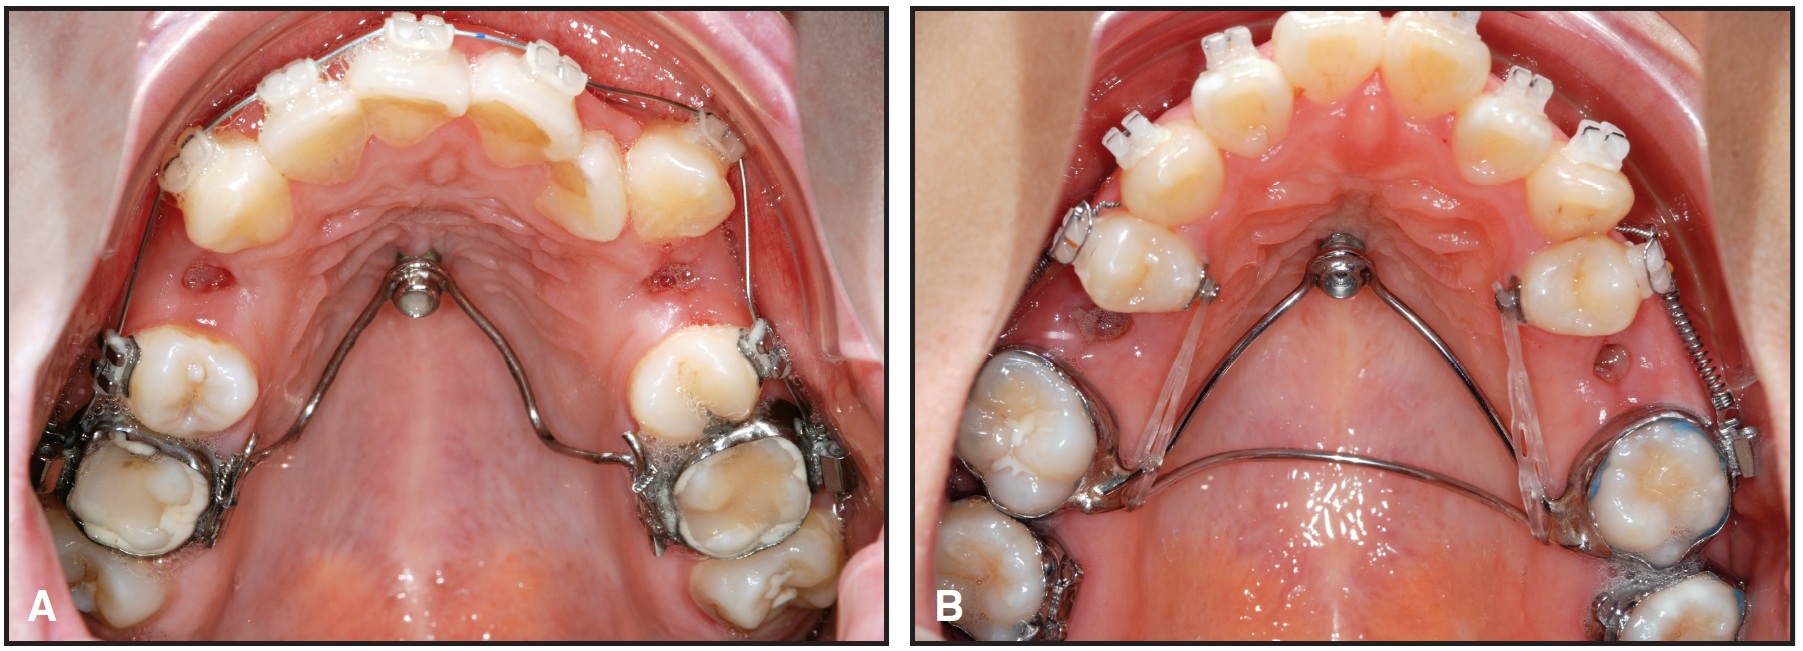

Fig. 8 Rapid maxillary expansion with hybrid Hyrax appliance, using anterior anchorage from two 2mm x 7mm Benefit mini-implants. Segmental buccal wires are added for simultaneous maxillary protraction with facemask.